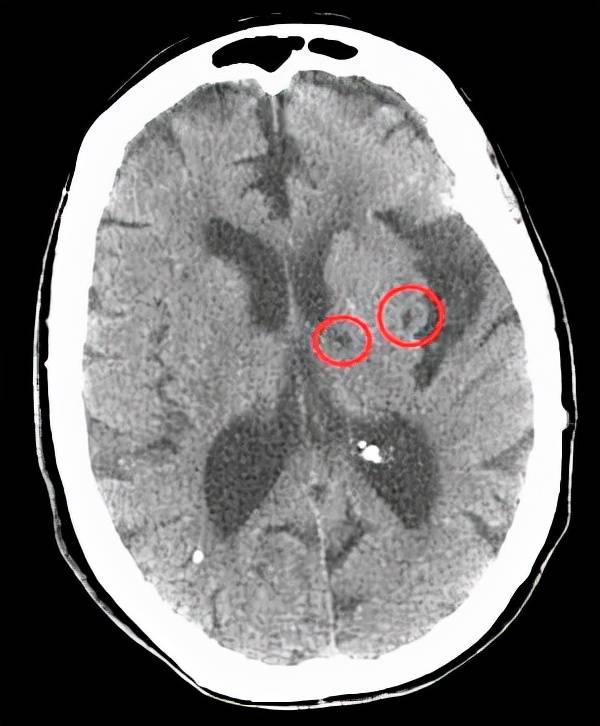

其实腔梗只是一个缩写 , 它的全名是腔隙性脑梗死 , 这种脑梗死的本质 , 其实是大脑血管中小动脉的闭塞而出现的脑组织损伤 。

一般来说范围在1.5厘米-2厘米之间 , 这个范围 , 我们都称之为腔隙性脑梗死 。

特别是在之后复查的影像学检查中 , 比如CT和核磁当中可以看到梗死之后的地方成为了一个天然的腔隙 , 所以因此得名腔隙性脑梗死 。